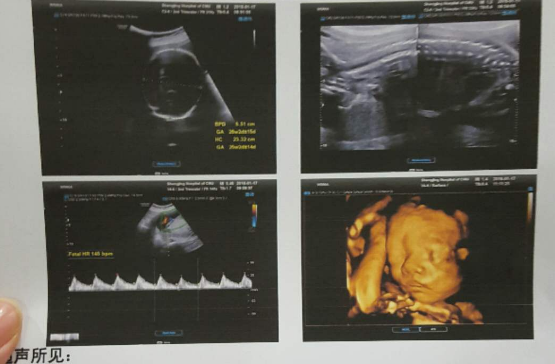

第三次B超检查

检查孕周:怀孕20-24周

这次产检中做B超主要是做“排畸检查”,现在不少医院是直接做四维彩超。

对于四维彩超孕妈们并不陌生,可以完整的对胎儿的发育情况进行成像,能准确的检测出胎儿的头面部、骨骼、内脏和神经系统的异常,但是有些异常如先天性白内障等是无法检查出来的。